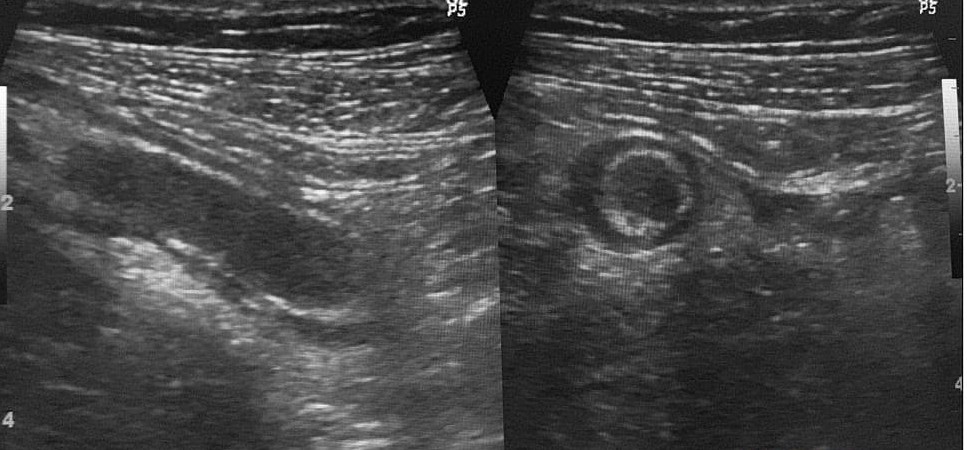

Hình ảnh ruột thừa viêm trên siêu âm, mặt cắt dọc và cắt ngang

Trên hình ảnh siêu âm, các dấu hiệu chính của viêm ruột thừa bao gồm:

– Ruột thừa tăng kích thước: Đường kính ruột thừa vượt quá 6mm.

– Thành ruột thừa dày: Thành ruột dày lên rõ rệt, thường lớn hơn 3mm.

– Không xẹp khi đè ép: Kỹ thuật đè ép bằng đầu dò không làm ruột thừa bị xẹp xuống, đây là một dấu hiệu quan trọng để phân biệt với ruột thừa bình thường hoặc các quai ruột khác.

– Thâm nhiễm mỡ: Các mô mỡ xung quanh ruột thừa bị phù nề

Các dấu hiệu khác có thể gặp bao gồm hình ảnh “Target Sign” (hình bia ngắm) hoặc “Finger Sign” (hình ngón tay), cũng như sự tăng sinh mạch máu trên siêu âm Doppler màu.